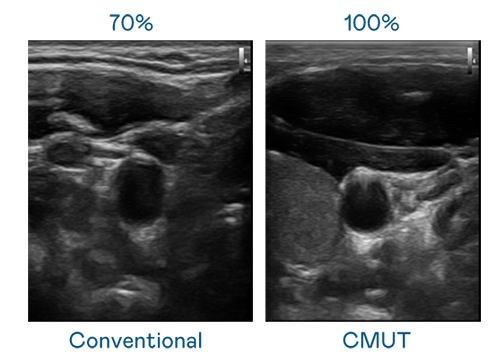

CMUT 技术是一种用电容式微机电元件来产生超音波讯号的技术。与传统 PZT 压电式技术相比,CMUT 频宽增加 30%,更宽频的超音波讯号让影像解析度大幅提升,是实现高影像品质医疗超音波扫描、促进精准医疗发展的关键技术。

大频宽带来超清晰影像

超音波影像的解析度高低,首先取决于探头能发出的讯号频宽。壹号娱乐 CMUT 可提供高清晰的超音波讯号,提供高频宽、高灵敏度、影像纹理细节更高的超音波影像,协助医护人员缩短影像判读时间及利用精准的医疗影像进行诊断。